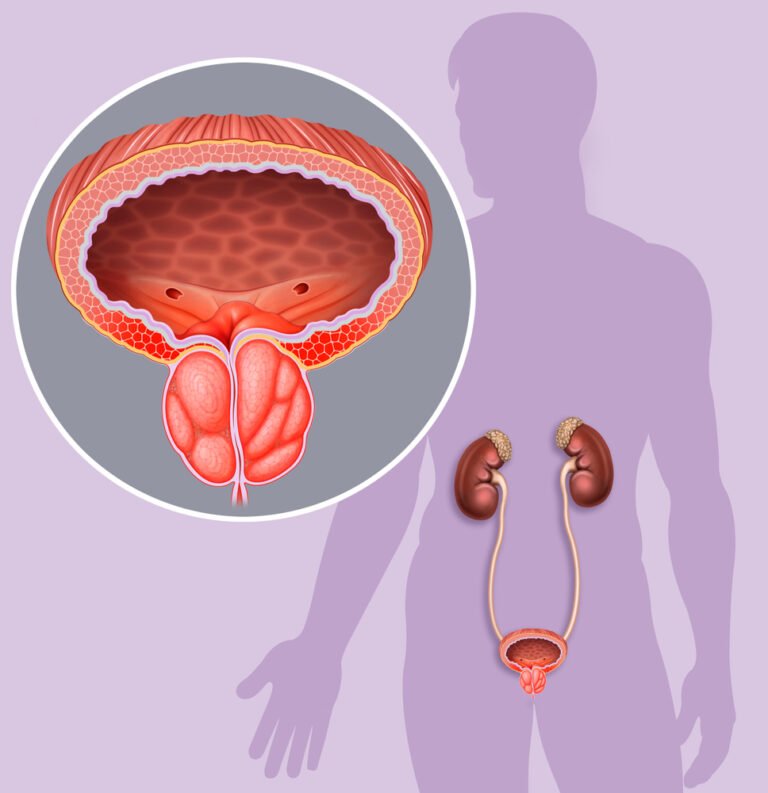

Frekuensi Buang Air Kecil yang Meningkat di Malam Hari

Sering terbangun tengah malam hanya untuk pergi ke kamar mandi merupakan sinyal awal gangguan pada saluran kemih. Kondisi ini memaksa otot kandung kemih bekerja lebih keras karena adanya tekanan dari kelenjar yang membengkak.

Pria yang mengalami nokturia biasanya merasa tidak nyaman karena waktu istirahat malam menjadi sangat terganggu. Pembesaran jaringan seringkali menjepit saluran uretra sehingga pengosongan cairan dari kandung kemih tidak pernah tuntas.

Tekanan konstan pada dinding kandung kemih menyebabkan keinginan untuk berkemih muncul berkali-kali dalam semalam. Keadaan ini lambat laun akan menurunkan kualitas tidur dan memicu kelelahan fisik yang cukup berat.

Aliran Urin yang Melemah Merupakan Tanda Kerusakan Prostat

Salah satu tanda kerusakan prostat yang paling mudah terlihat adalah melemahnya pancaran urin saat sedang berkemih. Aliran yang tersendat-sendat menunjukkan adanya sumbatan mekanis pada saluran yang melintasi bagian tengah kelenjar prostat.

Kejadian ini seringkali membuat proses buang air kecil memakan waktu lebih lama daripada biasanya bagi laki-laki. Tekanan kelenjar yang tidak normal menghambat laju cairan sehingga tenaga untuk mengeluarkan urin terasa jauh berkurang.

Urin yang keluar hanya berupa tetesan kecil menandakan otot kandung kemih sudah mulai mengalami kelelahan. Kondisi tersebut menunjukkan bahwa obstruksi pada saluran uretra sudah mencapai tahap yang cukup mengkhawatirkan.

Sensasi Nyeri atau Terbakar Saat Sedang Berkemih

Rasa perih yang muncul secara tiba-tiba saat urin keluar menandakan adanya iritasi atau infeksi yang serius. Bakteri seringkali berkembang biak dengan cepat pada saluran yang mengalami penyempitan akibat pembengkakan jaringan prostat tersebut.

Nyeri ini terkadang menjalar hingga ke area panggul atau bagian bawah punggung yang sangat menyiksa. Peradangan kronis yang tidak segera mendapat penanganan medis akan merusak sel-sel sehat di sekitar sistem reproduksi.

Rasa panas yang menyengat seringkali membuat pria merasa takut setiap kali ingin pergi ke toilet. Peradangan aktif ini memerlukan intervensi herbal atau medis agar infeksi tidak menyebar ke ginjal.

Kesulitan Memulai Buang Air Kecil Sebagai Tanda Kerusakan Prostat

Munculnya rasa sulit saat ingin mulai mengeluarkan urin merupakan tanda kerusakan prostat yang harus segera diwaspadai. Otot-otot di sekitar kandung kemih membutuhkan usaha ekstra kuat hanya untuk membuka katup saluran yang terhimpit.

Fenomena mengejan secara berlebihan saat di kamar mandi justru dapat memicu timbulnya wasir atau hernia. Hal ini menjadi bukti nyata bahwa kesehatan kelenjar sudah mulai mengalami penurunan fungsi secara perlahan namun pasti.

Hambatan mekanis ini seringkali membuat pria harus menunggu beberapa saat sebelum urin benar-benar bisa mengalir. Ketidaknyamanan tersebut merupakan indikator kuat bahwa kelenjar memerlukan nutrisi tambahan untuk meredakan ketegangan otot.

Munculnya Darah pada Urin atau Cairan Sperma

Kehadiran sel darah merah dalam cairan ekskresi menandakan adanya luka atau pecahnya pembuluh darah di prostat. Gejala ini memerlukan perhatian medis segera karena bisa saja menjadi indikasi awal pertumbuhan jaringan yang bersifat ganas.

Warna urin yang berubah menjadi kemerahan atau kecokelatan seringkali memicu kekhawatiran yang sangat besar bagi pria. Deteksi dini melalui pemeriksaan laboratorium sangat membantu untuk memastikan penyebab pasti dari munculnya darah tersebut secara akurat.

Luka pada jaringan dalam biasanya terjadi akibat gesekan antar sel yang meradang secara terus menerus. Penanganan yang cepat dapat mencegah kerusakan permanen pada sistem vaskular di area sekitar kelenjar.